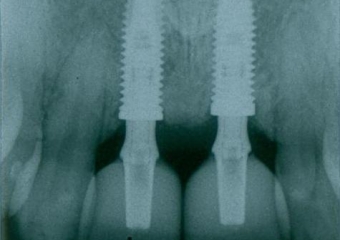

IImagem com as próteses definitivas em porcelana

Próteses Definitivas em Porcelana

Sorriso Final, em 2016